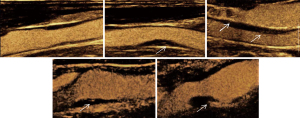

Shear wave elastography was used to measure the YM values (see Figure 2). Additionally, the direction of contrast agent diffusion in the plaque was categorized as internal-external or non-internal-external (where “internal” refers to the artery lumen, and “external” refers to the outer membrane of the artery).

A typical manifestation of an ulcer is the flow of contrast agent from the lumen into the concavity of the plaque-lumen boundary, accompanied by arterial lumen enhancement. The diffusion of micro-vesicles from the artery lumen into the plaque manifests as moving bright spots or lines from the inside or out. Studies have confirmed that contrast agent diffusion is related to plaque rupture (7,9).